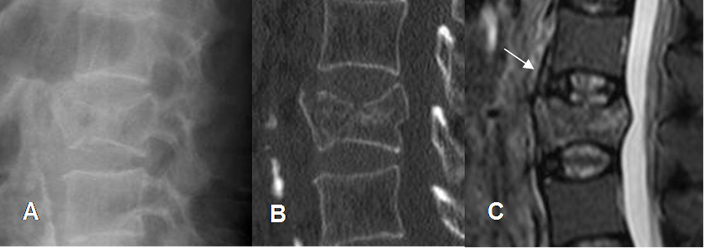

Fig 187. Lesión ligamentaria.

A: Rx lateral, B: TAC reconstrucción sagital y C: RM sagital en STIR. Fractura vertebral inestable, con fragmentos antero y retropulsados. El ligamento común anterior está elongado y con áreas hiperintensas, por ruptura parcial.